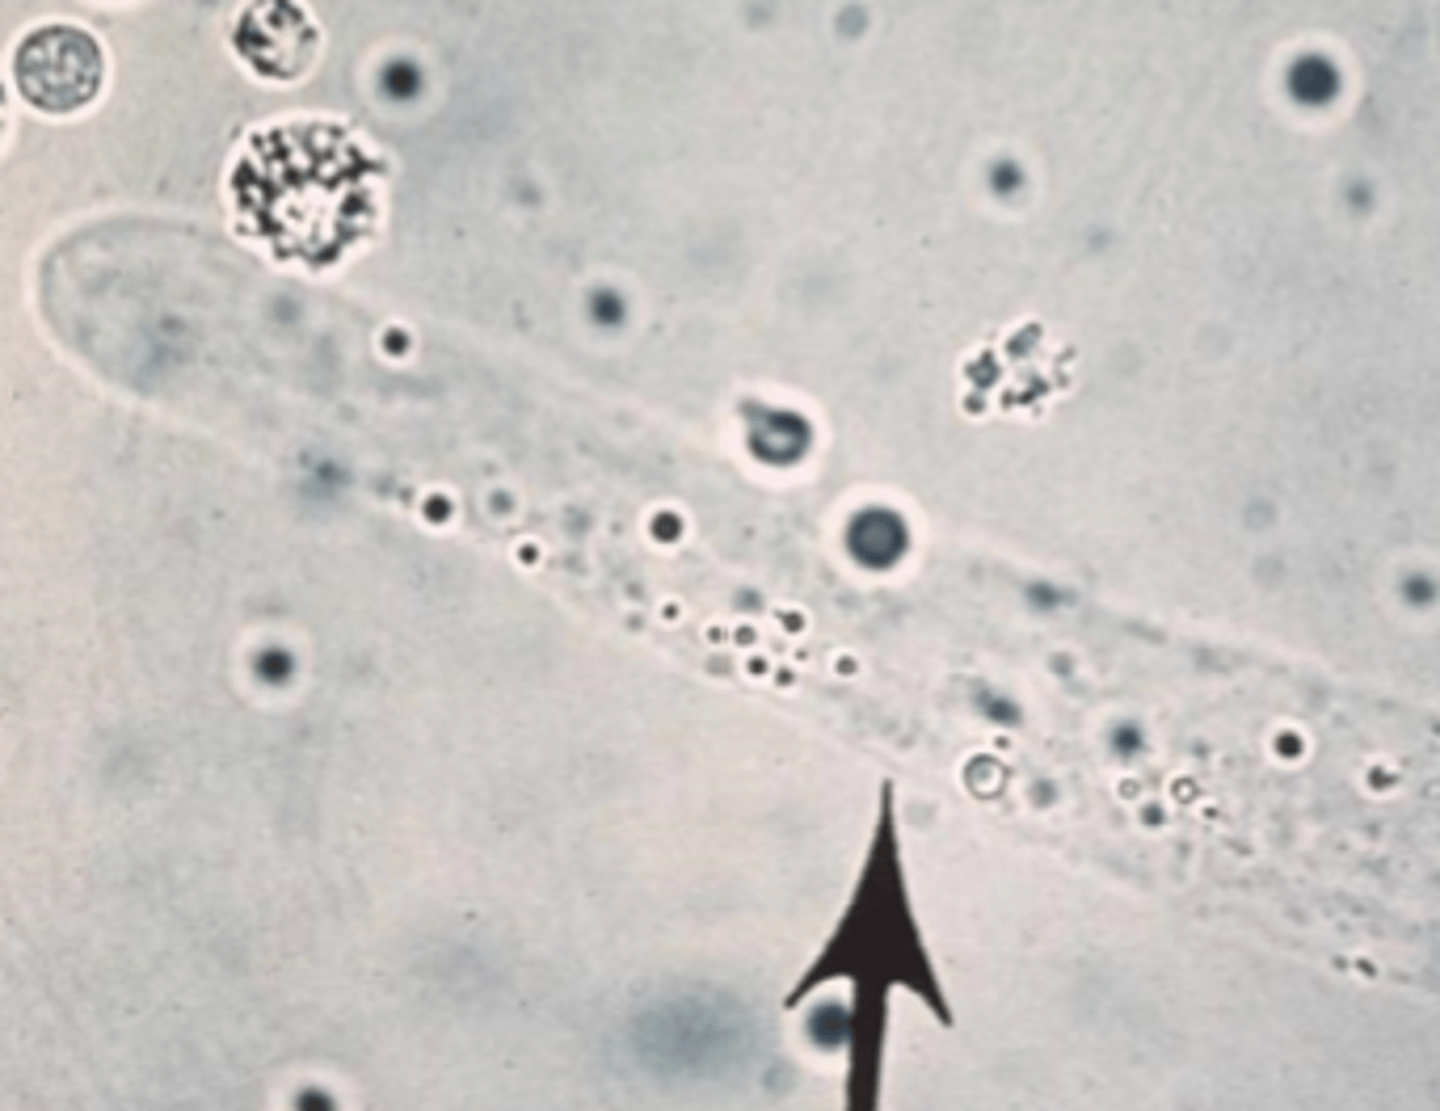

aggregate reticulocytes

orange arrow

hint: NMB stain

punctate reticulocytes

**not counted

green arrow

hint: NMB stain